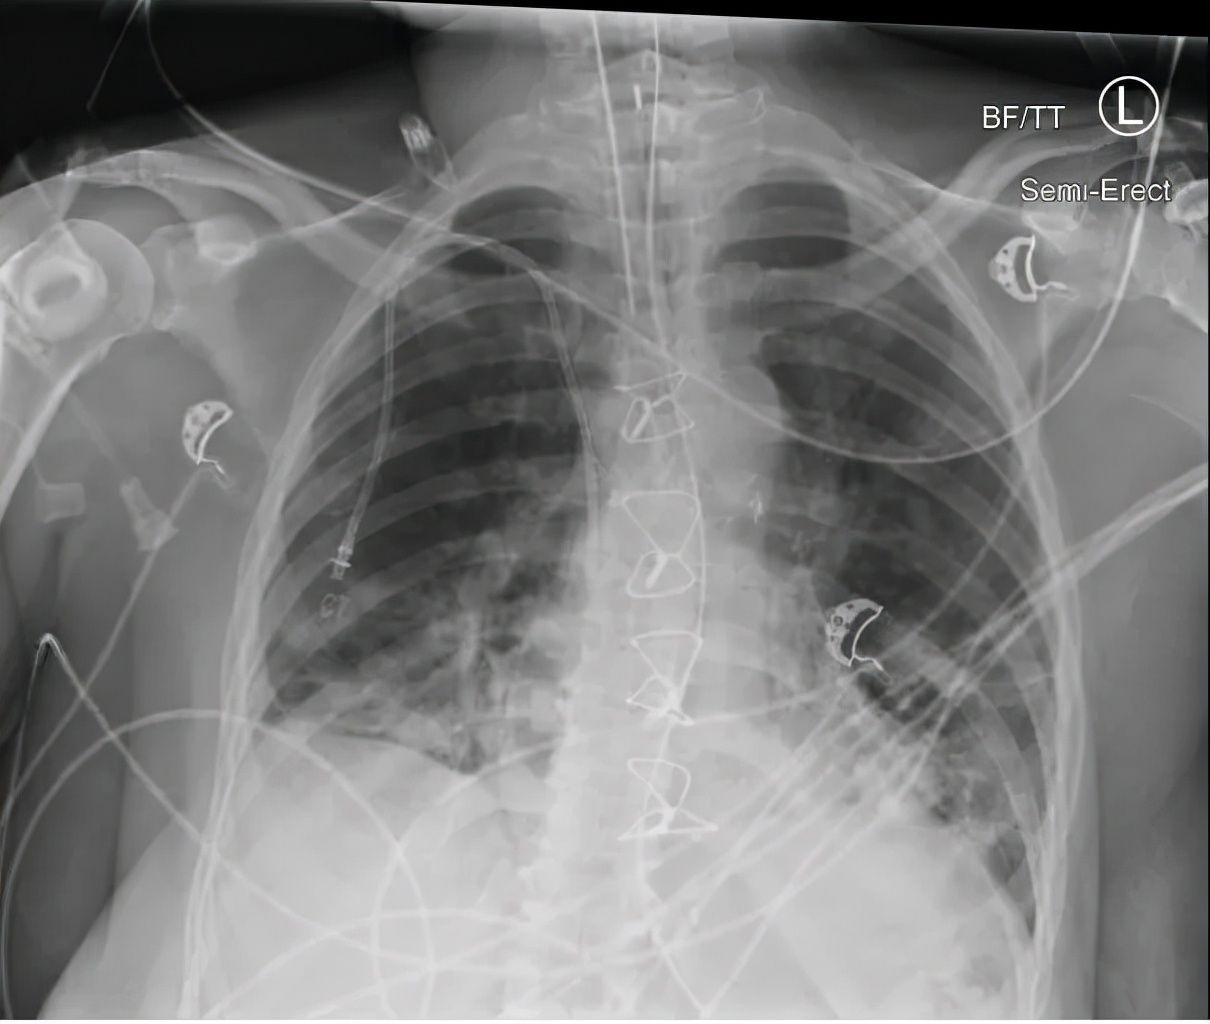

文章插图

拒绝疫苗A女士的肺移植很成功。移植后,A女士的医疗照护全部转到了肺移植团队,再没有来过我的门诊。但我知道,在移植后的若干年里,她的移植肺功能很好。随着孩子们的逐渐长大,A女士甚至可以参加一些社会活动。但是,近三年左右,移植肺开始出现缩窄性气道病变(目前肺移植几乎无法避免的最终并发症),A女士的行动又逐渐开始受限,基本回到了接近移植前的功能状态。移植团队曾经正式讨论过再次移植的可能性,因为A女士此时也就才不到五十,而且其它器官系统功能均没有大异常。

终于,三周前,A女士感染了新冠肺炎,很快转为重症。移植团队通知我时,她的缺氧已经严重到了必需呼吸机支持的程度。可是,她此时却已经签署生存遗嘱,选择了DNR。DNR是一种医疗状态代号,全称为,不要抢救(Do Not Resuscitate),即,如果出现呼吸循环衰减时不要抢救。自然,DNR包括了不要气管插管,不要人工呼吸支持。